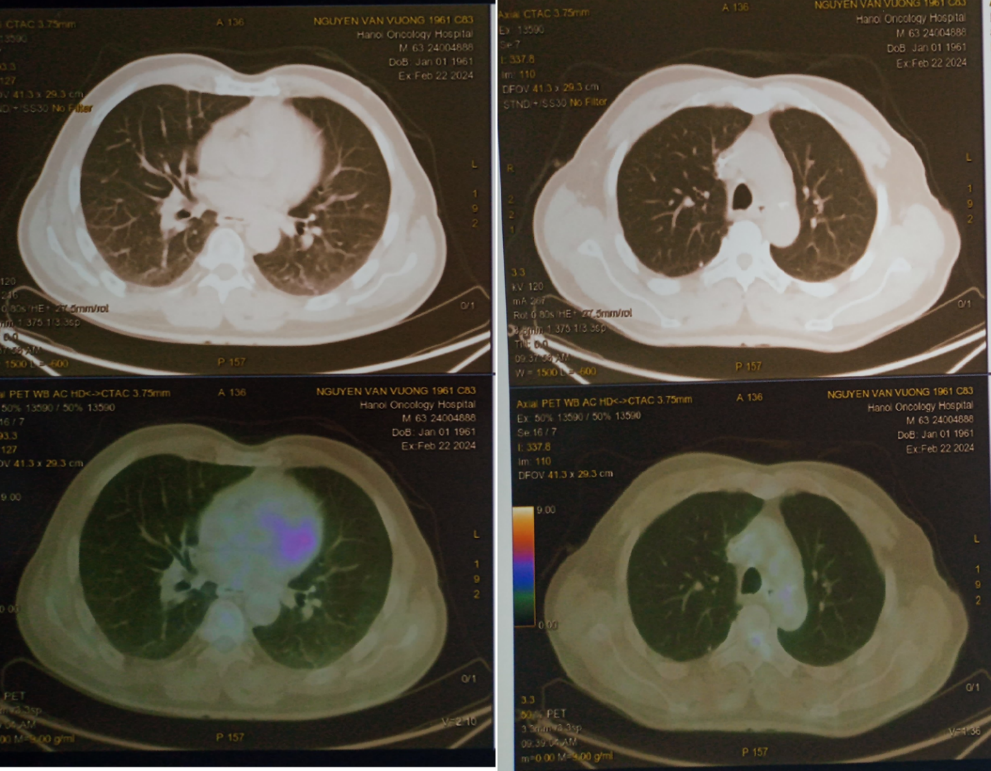

- Hình ảnh chụp PET/CT đánh giá giai đoạn trước điều trị:

Hình 1: Hình ảnh tăng chuyển hoá FDG ở nhiều vị trí hạch cả ở trên và dưới cơ hoành.

Hình 2: Hình ảnh tổn thương phổi phải không tăng chuyển hoá FDG nhưng chưa loại trừ thứ phát

Hình 3: Hình ảnh hạch bất thường trung thất và hạch nách

- Hình ảnh nhiều hạch cổ (nhóm II, III, IV, V) hai bên ưu thế bên phải, hạch lớn nhất kích thước 24x34 mm, tăng chuyển hoá F-18 FDG (SUVmax: 26.09)

- Hình ảnh 2 nốt đặc bờ đều ở thuỳ trên phổi phải, kt 19x27 mm và 10x12mm

- Hình ảnh nhiều hạch trung thất ở trước các mạch máu lớn, cạnh khí quản, dưới quai, trước và dưới carina, hạch lớn nhất kích thước 25x18mm, tăng chuyển hoá FDG.

- Hình ảnh nhiều hạch rốn phổi, hạch lớn kích thước 15x18mm, tăng chuyển hoá FDG.

- Hình ảnh nhiều hạch hố nách 2 bên, hạch lớn kích thước 21x40mm, tăng chuyển hoá FDG.

- Nhiều hạch ổ bụng quanh động mạch chủ, hạch chậu trong 2 bên, chậu ngoài bên trái, hạch lớn kích thước 39x40mm, tăng chuyển hoá FDG.